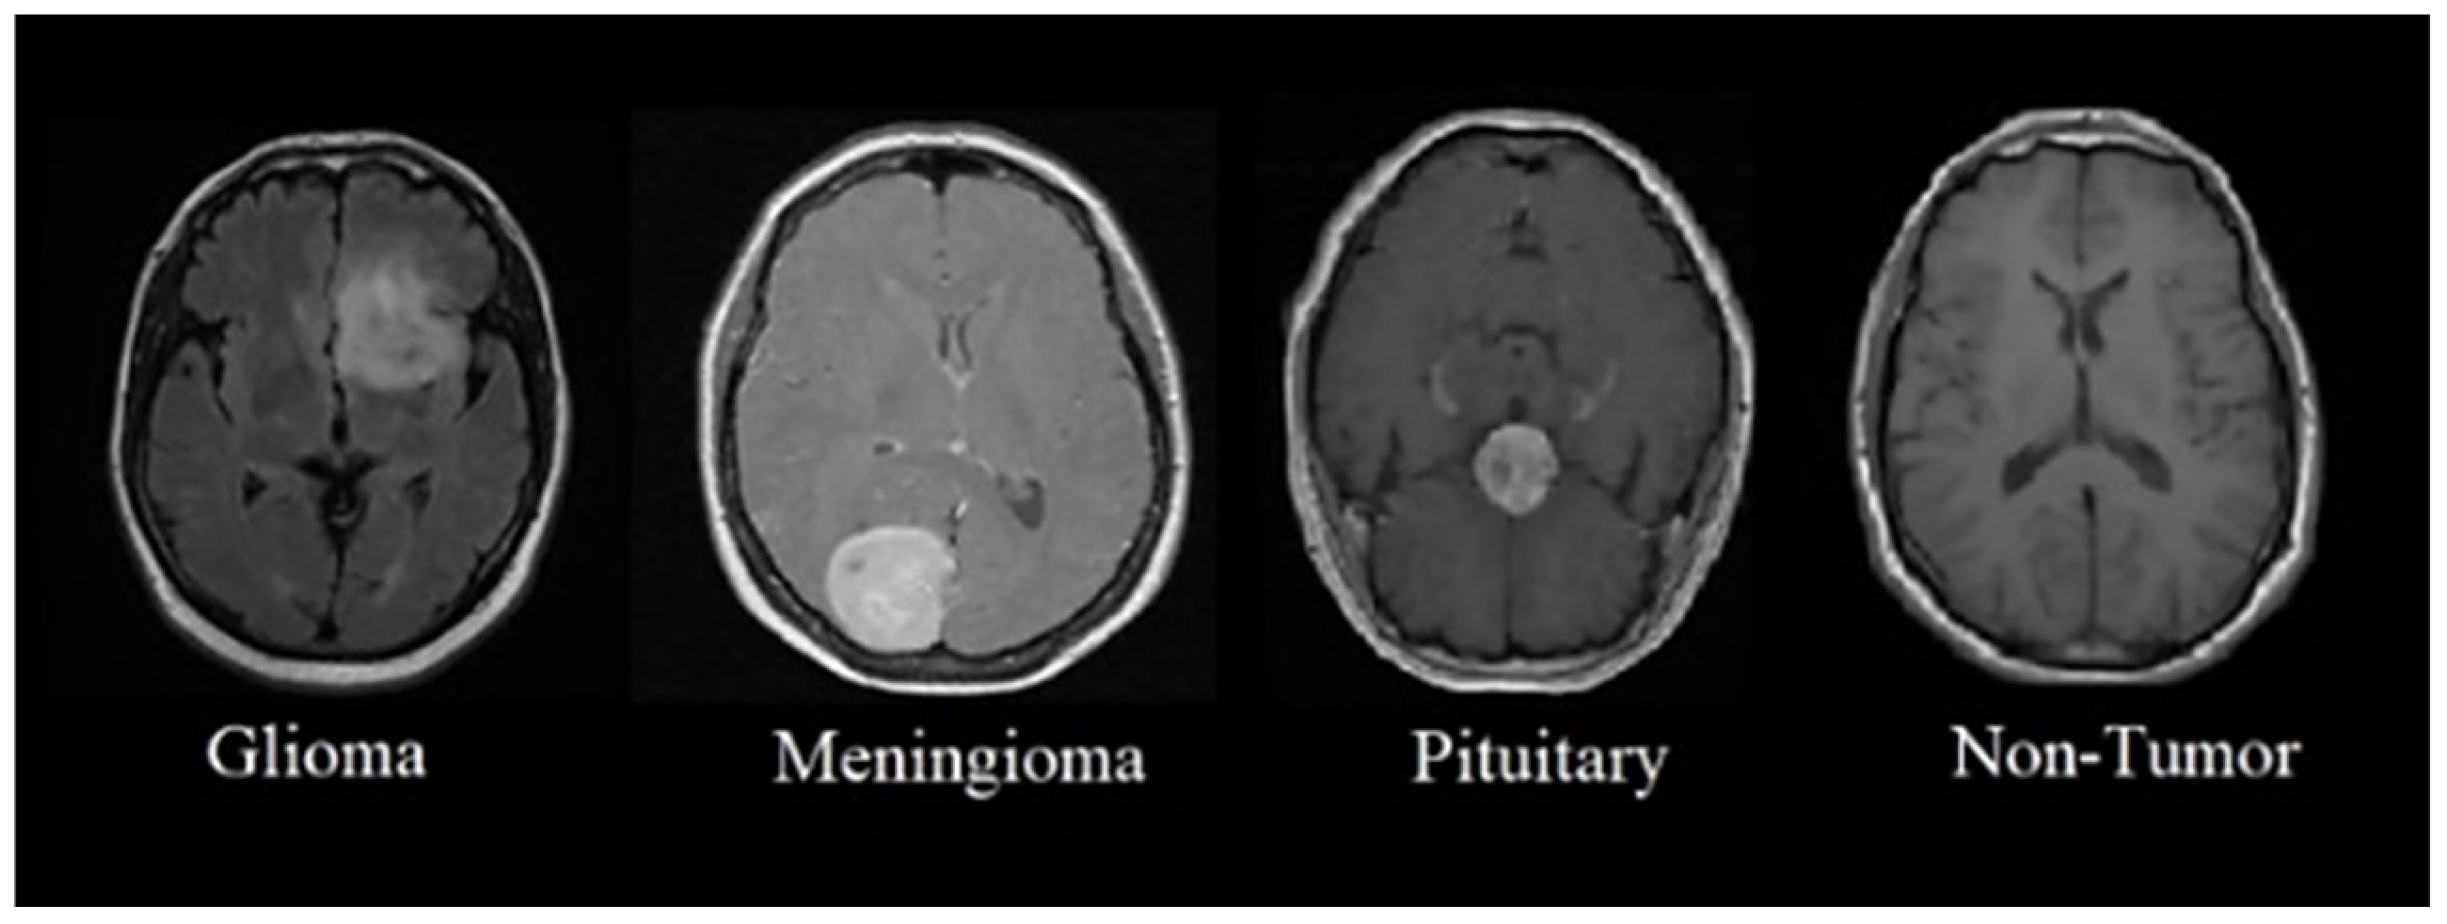

4.1. Dataset